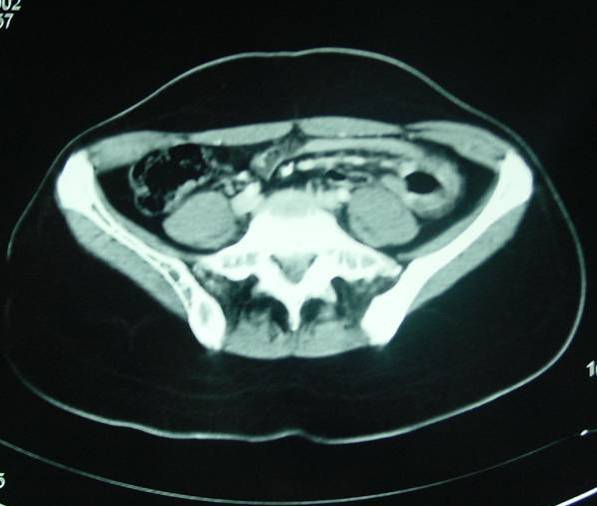

İleri Radyolojik Yöntemler

• Bilgisayarlı tomografi (BT)

• Manyetik rezonans görüntüleme (MR)

• Özellikle kitle oluşturan lezyonlarda.

• İlk aşamada kullanılmaları önerilmez.

• Konulmuş olan bir tanı sonrası yaklaşımı planlamada yardımcı olurlar.